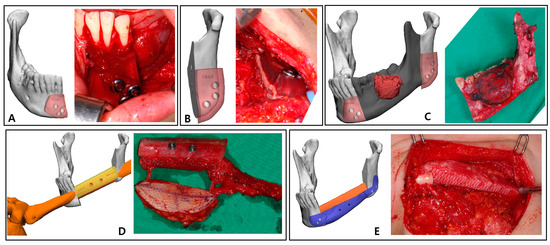

The preoperative patient’s craniomaxillofacial skeleton and lower extremities region-enhanced CT images with slice thicknesses of 1.0 mm were stored in the digital imaging and communication in medical (DICOM) format. These datasets were imported into medical simulation software (Mimics, Materialize NV, Leuven, Belgium) to generate the skull and fibula models through segmentation processing. The standard tessellation language (STL) files of these 3D objects were transferred to medical CAD software (3-matic®, Materialize NV, Leuven, Belgium). The mass was extracted by overlapping the enhanced MRI data with the CT data (Figure 2A), and, based on this, the resection part, including the first premolar to the mandibular notch, was determined with a proper safety margin.

After performing the planned mandibulectomy on the software, mandible cutting guides were designed to implement it (Figure 2B). The left fibula model was moved to the resection area, and the fibula model was positioned at the alveolar level to facilitate later implant placement, considering the fibula’s shape and pedicle location. To achieve this, the fibula cutting guide and the fibula positioning guide were created (Figure 2C,D). In the inferior part, the scaffold that reproduced the original shape of the patient’s mandibular border was designed to partially cover the outer and lower side of the fibular segment to recreate the volume, and, at the same time, it was intended to support the position of the fibula more accurately (Figure 3). Wing-shaped connection parts with fixation holes that could be fixed to the remaining mandible were added on both sides of the scaffold (Figure 2E). All surgical guides and the scaffold were designed to be fixed with screws through fixation holes, and the locations of these fixation holes were shared to enable reconstruction (Figure 2F).

Figure 2. Preoperative 3D simulation for designing surgical guides and patient-specific PCL implant: (A) Mandible model generated from the patient’s CT data and tumor (red) isolated from MRI data; (B) Resection margin (dark gray) with sufficient safety margin and mandible cutting guides (pink) to reproduce it; (C) Left fibula model was moved to the most ideal position at the alveolar level, and the fibula cutting guide (yellow) was designed. (D) Fibula positioning guide (sky blue); (E) PCL scaffold design (blue) to recreate the mandible border below the fibula segment; (F) Fixation holes of all surgical guides are planned to share position vectors (green).